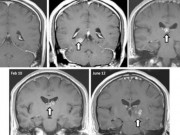

Nằm trên giường bệnh, Duyên nói rằng bản thân không hề biết mình mắc bệnh. Gần đây khi công ty cho đi khám sức khỏe, bác sĩ kiểm tra phát hiện gan của Duyên có tổn thương nghi do ký sinh trùng làm tổ. Sau đó, Duyên được chuyển xuống BV Đặng Văn Ngữ kiểm tra và bác sĩ chẩn đoán bị sán lá gan.

Trước đó người đàn ông này cảm thấy ăn không ngon miệng, đau vùng thượng vị nhiều, đi khám ở địa phương phát hiện có vật thể nghi là ký sinh trùng ở lá lách. Khi đến bệnh viện, ông Chiến làm xét nghiệm, kiểm tra và được chẩn đoán bị sán lá gan nhưng đi lạc chỗ lên lá lách. Hiện ông Chiến vẫn đang được điều trị.